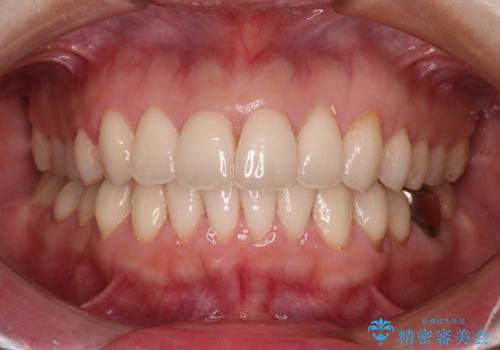

- 上下の前歯のデコボコを気にして来院された患者様です。

妊娠中であり、途中通院が難しくなる可能性があることから、インビザラインによる矯正治療を行うこととしました。

上下顎歯列全体の後方移動とIPR(歯と歯の間を削る)によってデコボコが解消するように設計しました。